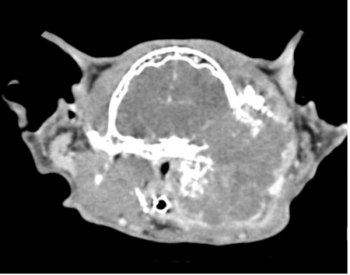

CT and MRI continue to gain traction as they become more widely available and less costly. Their diagnostic superiority over radiography will improve the treatment of some common diseases in small animal patients.